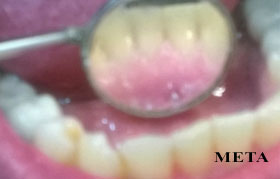

PHOTO GALLERY